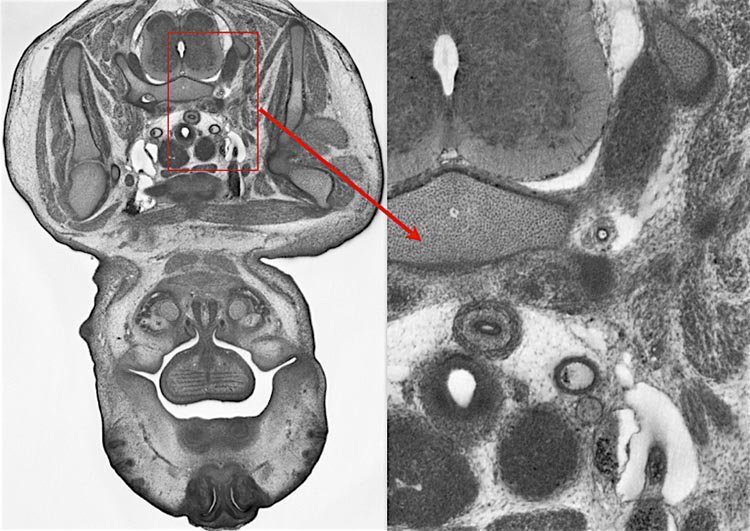

The DMDD research programme produced a free, online database of embryonic-lethal mouse gene knockouts, including high-resolution 3D images and phenotype data.

Former Deciphering Mechanisms of Developmental Disorders project members in Vienna are running a 2 day workshop on HREM imaging, its applications, sample preparation, data generation and analysis, challenges and limitations. 23-24 May 2019. blog.dmdd.org.uk/hrem-workshop/ #hrem #imaging #development #Microscopy

The other is out Nature Communications doi.org/10.1038/s41467… This work was part of the Deciphering Mechanisms of Developmental Disorders programme which has phenotyped embryonic lethal mouse mutants. (1/11)